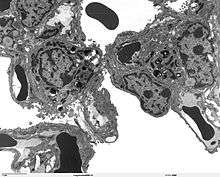

The protein encoded by this gene (SP-A2) is primarily synthesized in lung alveolar type II cells (see type II pneumocyte), as part of a complex of lipids and proteins known as pulmonary surfactant. The function of this complex is to reduce surface tension in the alveolus and prevent collapse during expiration. The protein component of surfactant helps in the modulation of the innate immune response, and inflammatory processes.[4]

The lung is the main site of SFTPA2 synthesis, but SFTPA2 mRNA expression has also been detected in the trachea, prostate, pancreas, thymus, colon, eye, salivary gland and other tissues. While the majority of these tissues express both SFTPA2 and SFTPA1 transcripts, only SFTPA2 expression was found in the trachea and prostate.[12] Using specific monoclonal antibodies for Surfactant protein A, the protein can be detected in lung alveolar type II pneumocytes, Clara cells, and alveolar macrophages, but no extrapulmonary SP-A immunoreactivity was observed.[12]